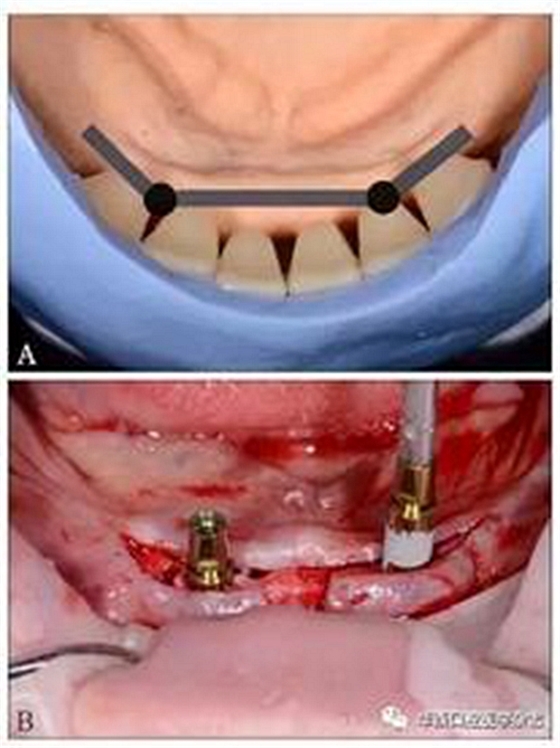

(3)制定治療計劃:黏膜支持式總義齒修復上頜無牙頜;種植體-桿卡固位覆蓋義齒修復下頜無牙頜。根據人工牙的排列設計桿的位置,使桿位于牙槽嵴與人工牙間,并設計種植位點(圖3A);運用雙側游離端短懸臂,增加義齒穩(wěn)定與固位[9,13]。依診斷排牙翻制種植手術導板。

(4)種植手術:依據種植手術導板,在下頜雙側側切牙與尖牙之間的位點各植入1枚3.8 mm×11 mm種植體(XIVE,F(xiàn)riadent公司,德國),植入扭矩25 N·cm(圖3B)。